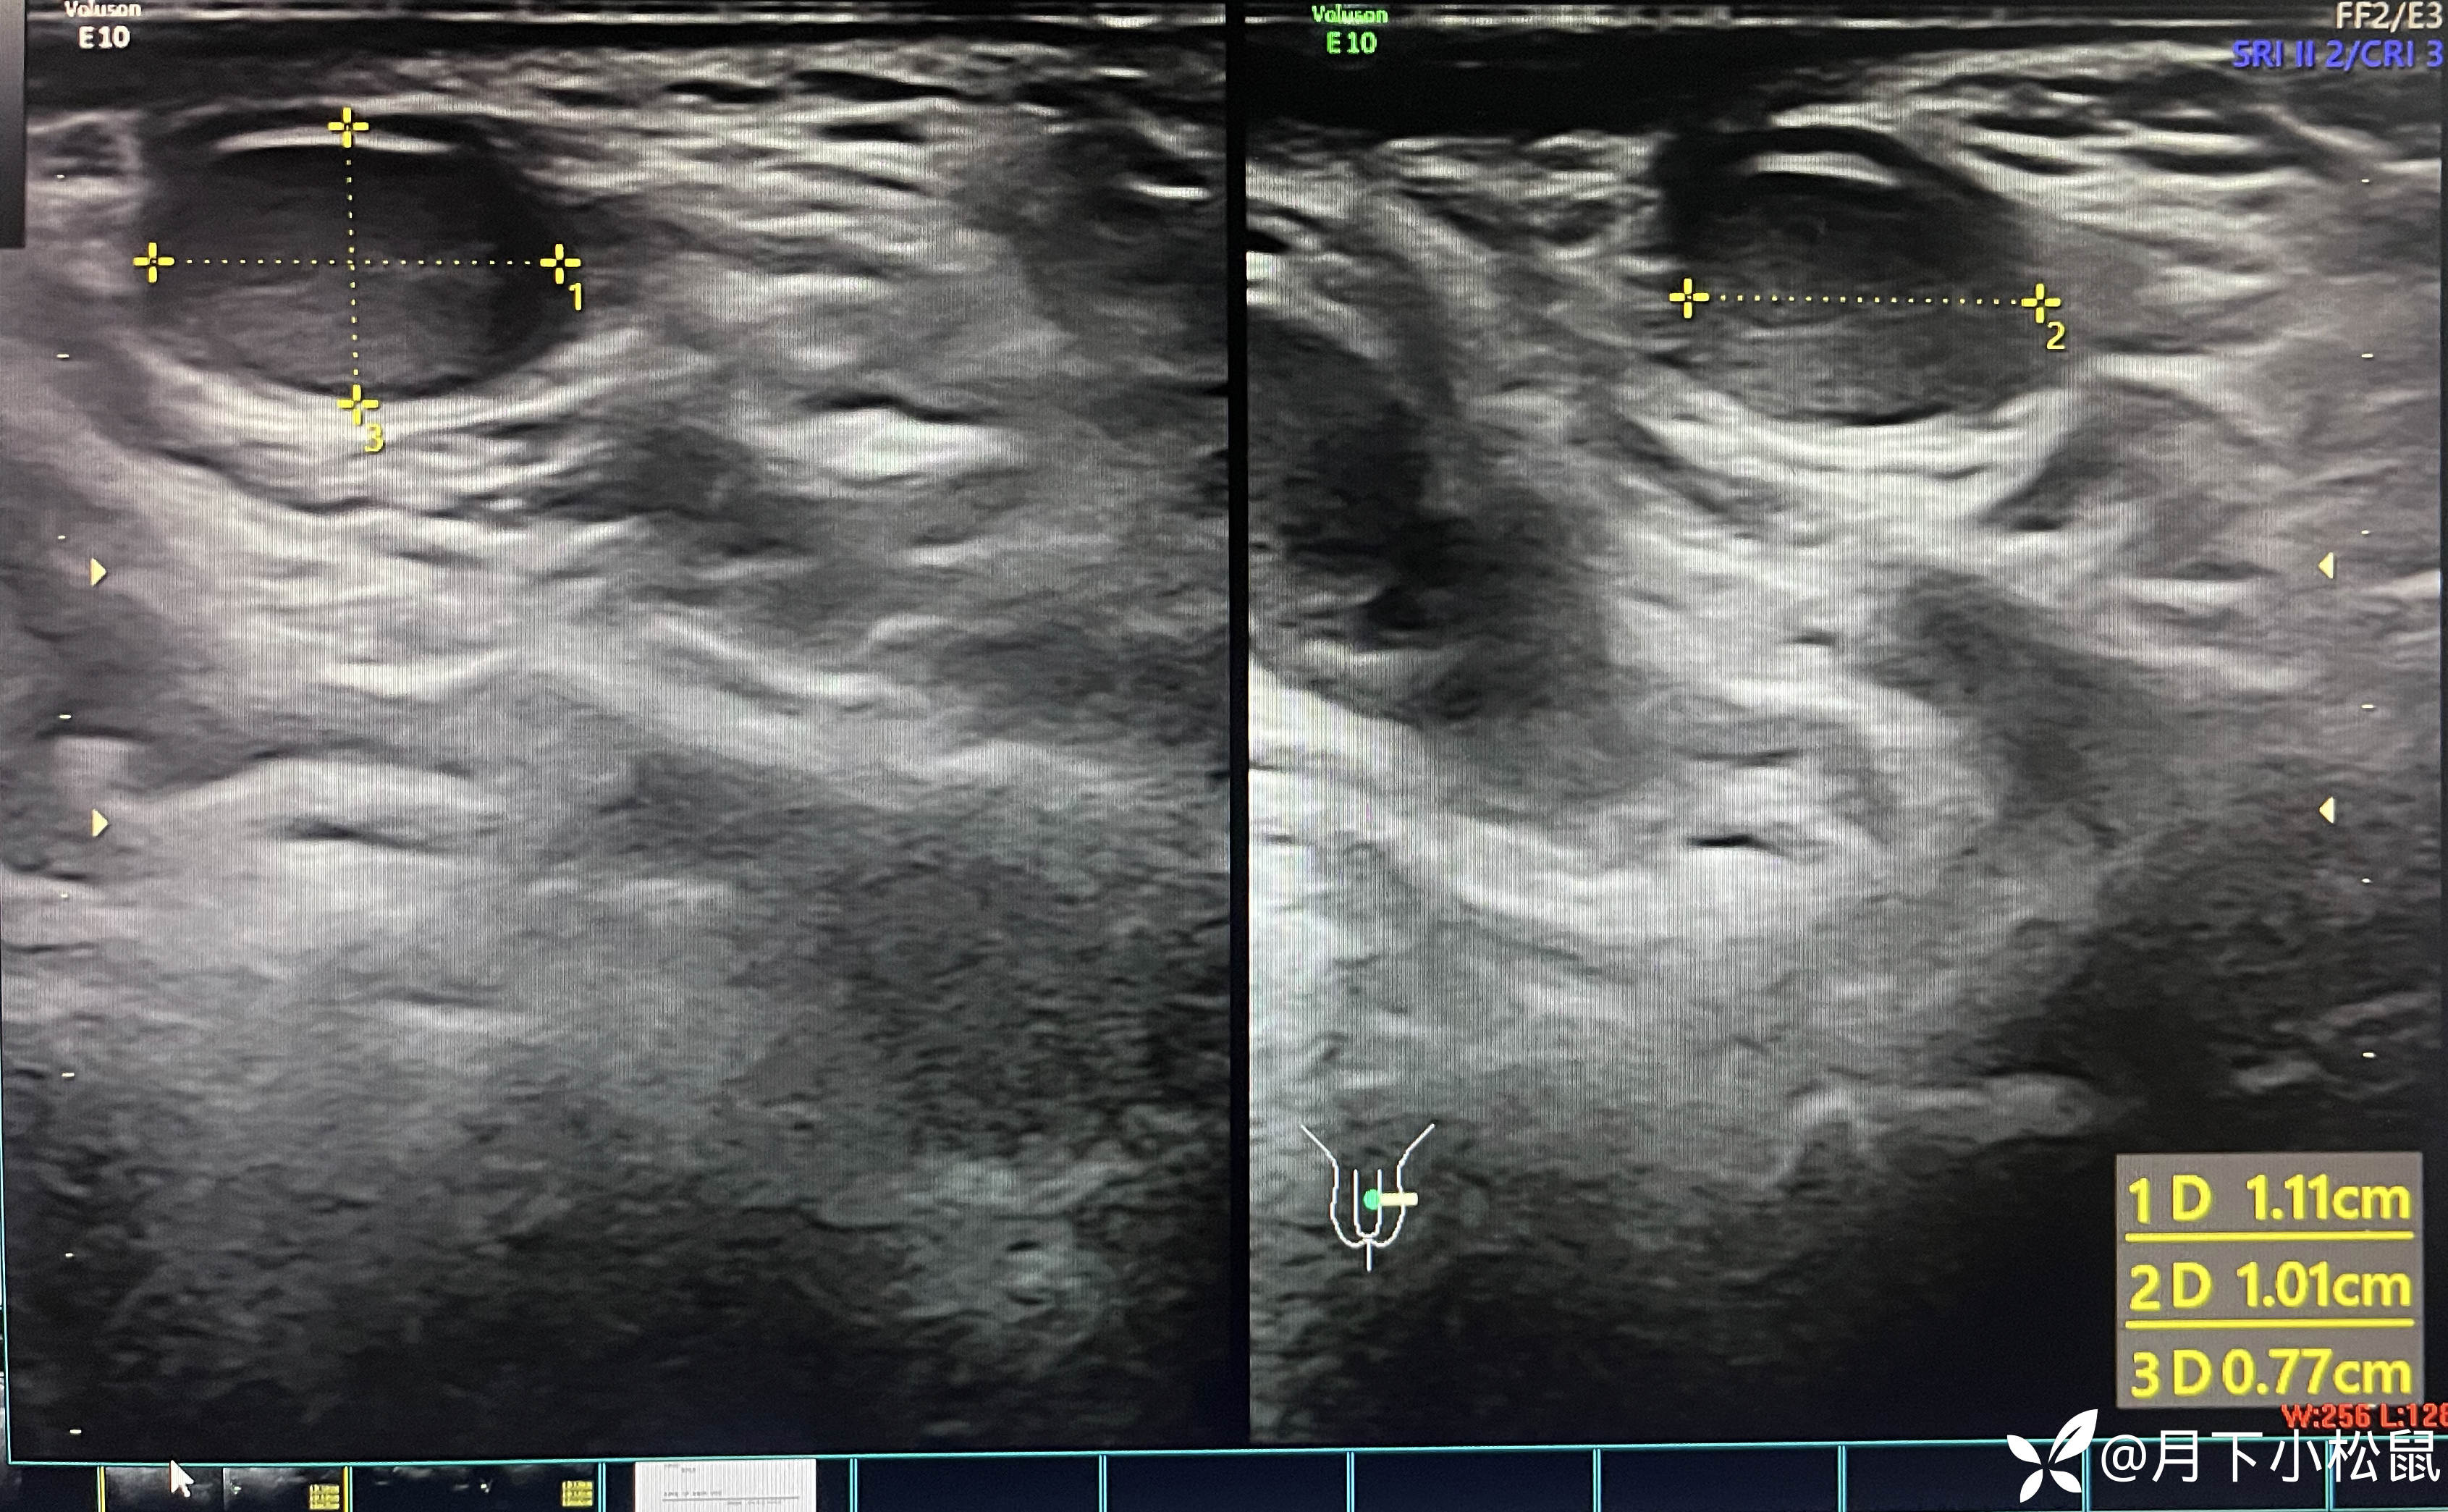

给开了B超,申请单上面写了详细的体格检查内容,同时嘱家属在做B超时一定和做B超的医生说仔细看看蛋蛋。

腹部B超检查报告回报示:

报告:

学习专家共识后,回归到该名小患者本身,该患儿诊断为“左侧隐睾”,建议尽早至小儿外科进行手术治疗,并定期随访复查。